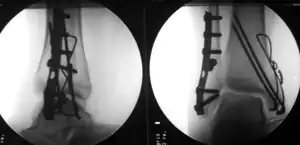

| Surgically treated bimalleolar fracture | |

Surgical treatment will often be required, usually an Open Reduction Internal Fixation (ORIF). This involves the surgical reduction, or realignment, of the fracture followed by the implementation of surgical implants to aid in the healing of the fracture.[2]